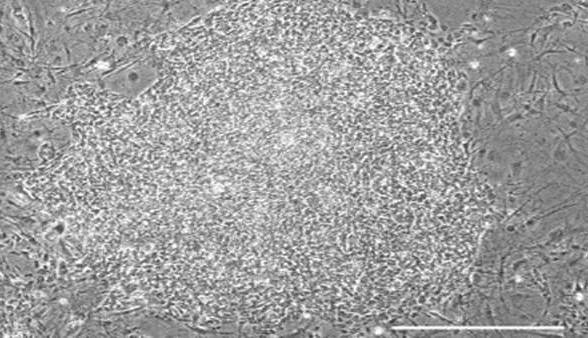

تبدیل سلولهای بنیادی به سلولهای استخوانی

دانشمندان دانشگاه RMIT توانستهاند با استفاده از امواج مکانیکی با فرکانس بالا (در حد مگاهرتز)، [...]